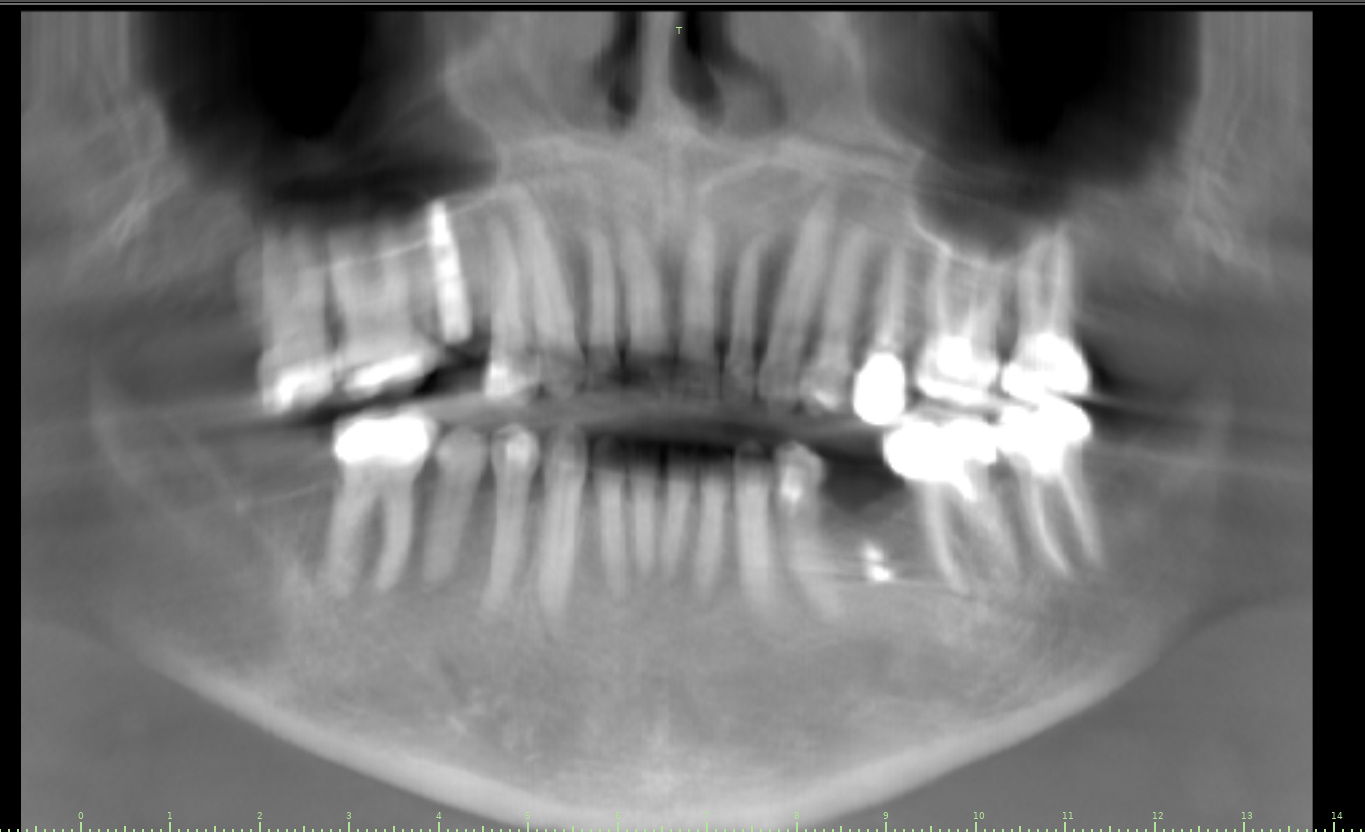

Surgical program case from Dental Implant Institute